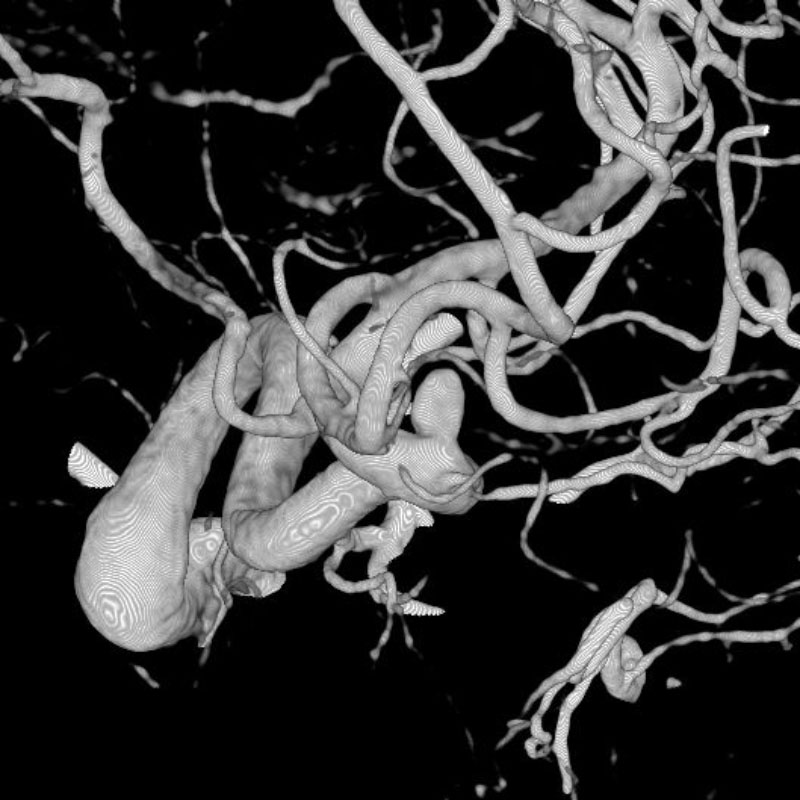

脳動静脈奇形

血管塞栓術

松田/濵田/元永